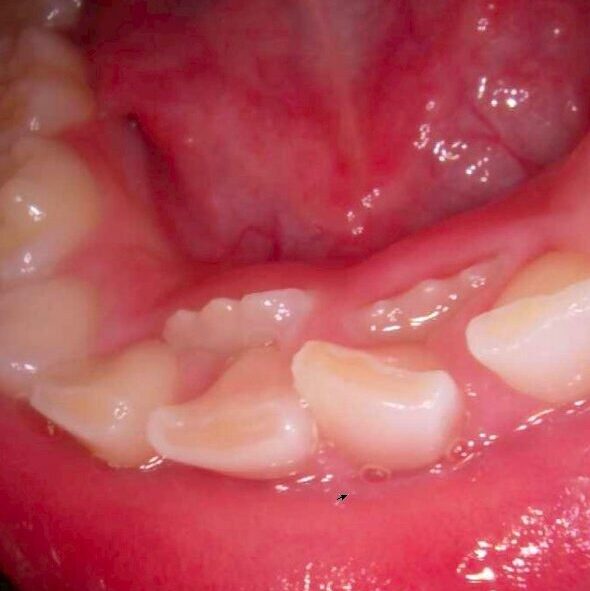

通常、永久歯は乳歯の真下から生えてきて、乳歯を自然に押し出すようにして生え替わります。しかし、中には乳歯が抜ける前に永久歯が内側(裏側)から生えてくるケースがあります。これを「二重歯列」とも呼びます。

この現象は、永久歯が予定よりも内側から萌出した場合や、乳歯の根が吸収されにくいことが主な原因です。永久歯の生える方向やスペースの不足、顎の小ささなども関係していることがあります。

前歯の生え変わり期(5〜7歳ごろ)に、乳歯がまだ残っているにもかかわらず、裏側から歯が生えてきているのを見つけたら、早めの歯科受診をおすすめします。上下どちらかの前歯で起きやすく、噛み合わせに影響を及ぼす場合もあります。